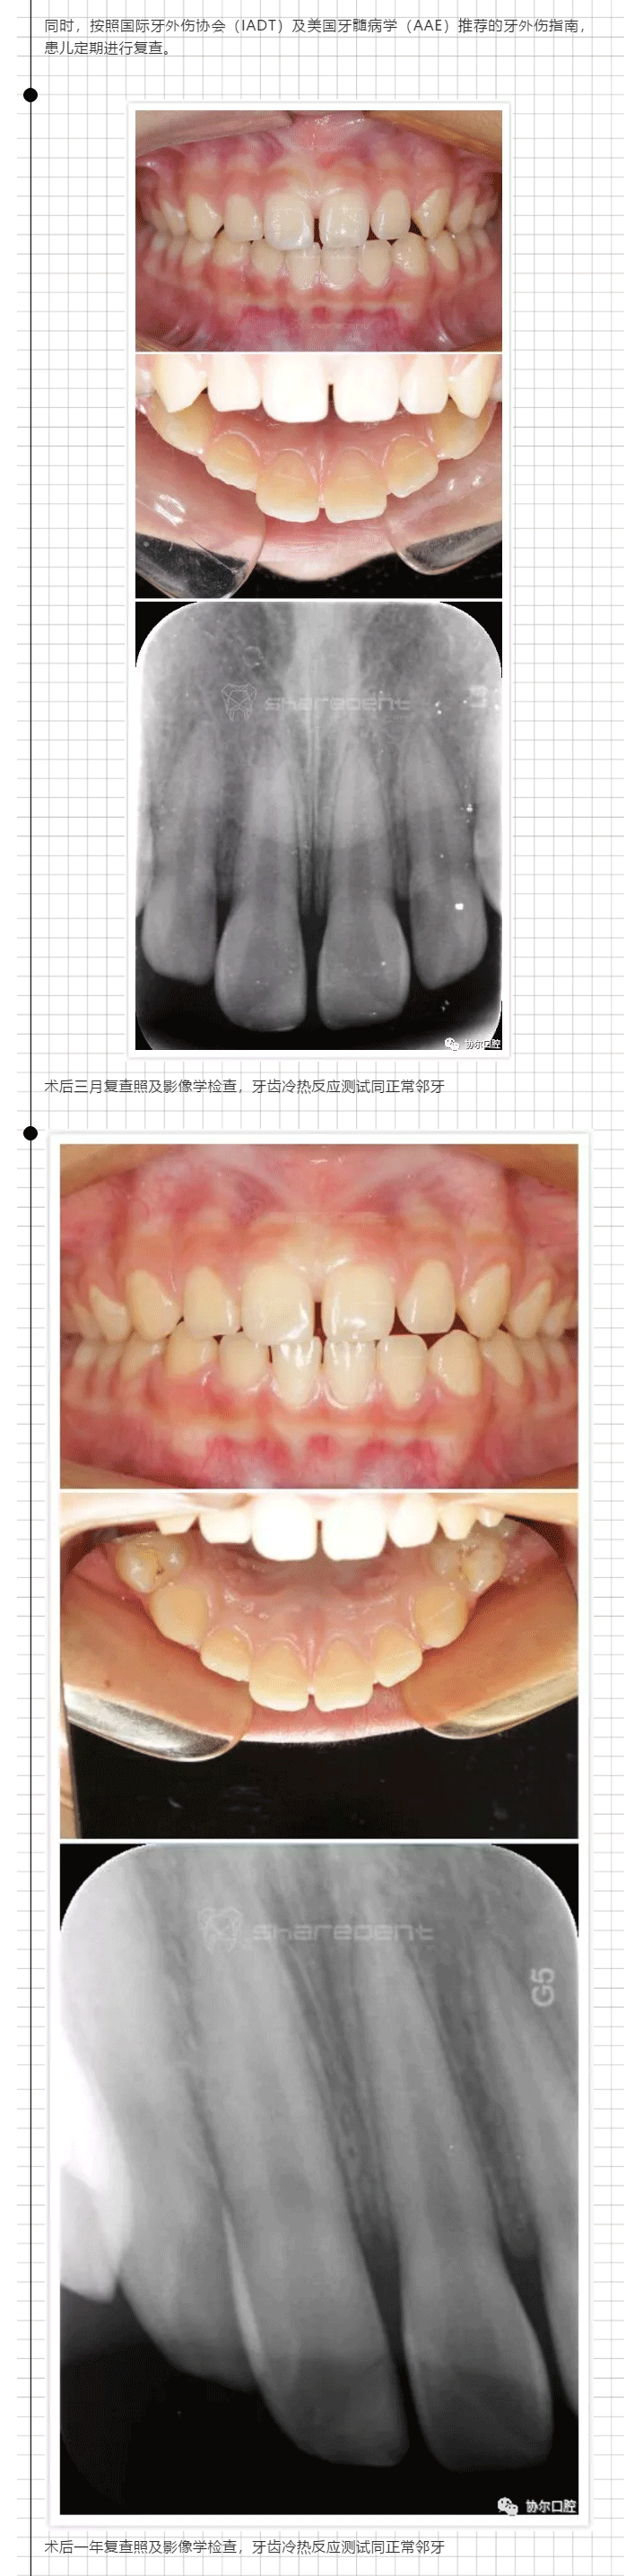

儿童牙齿折断没法处理!等到18岁?来协尔吧